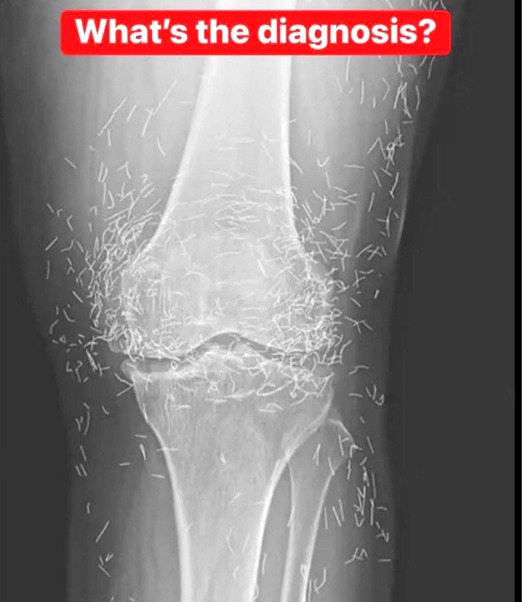

X-Ray Reveals Hundreds of Gold Needles in Woman’s Knees

Doctors examining a 65-year-old South Korean woman’s X-ray were shocked to find hundreds of tiny gold acupuncture needles embedded in her knees.

Her practitioner had intentionally left the gold needles in her tissue for continued stimulation. However, experts warn this can cause inflammation, abscesses, infection, and interfere with imaging scans like X-rays or MRIs.